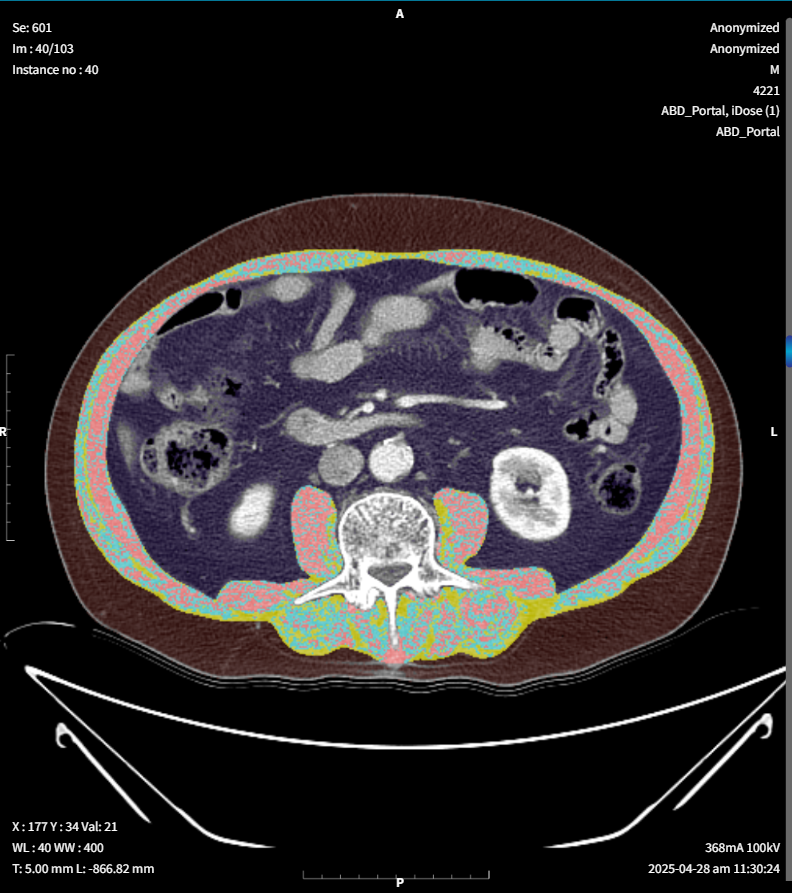

근육과 지방 자동 분석

근육 지방 분석

분석 정확도

근육/지방 구분 정확도 (Dice score)

2.7%

오차율

실제 면적 대비 평균 오차